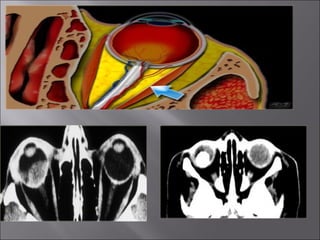

Ultrasound and CT scans provide anatomical images of the orbit, while color Doppler imaging provides visualizations of vascular structures and blood flow within lesions. These imaging techniques are used to evaluate a variety of orbital conditions involving blood vessels, infections, tumors, congenital issues, trauma, and more, and can help identify vascular disorders, thrombosis, treatment responses, and dynamic changes in benign tumors over time.